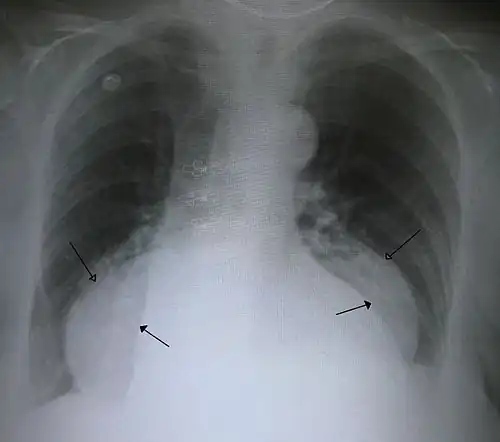

A large hiatal hernia on chest X-ray marked by open arrows in contrast to the heart borders marked by closed arrows

This hiatal hernia is mainly identified by an air-fluid level (labeled with arrows). -